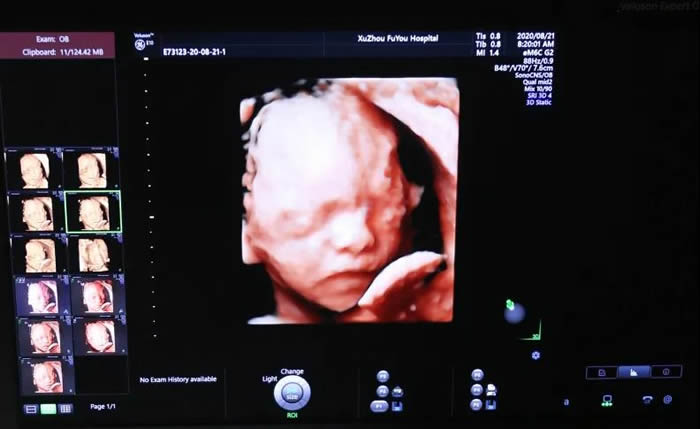

張麗主任介紹,無論是三維還是四維,都是在二維超聲的基礎上,利用計算機再處理技術達到立體模式重建的超聲診斷技術,能看到胎兒的立體圖形。“也就是說,三維彩超好比照相機,能捕捉胎兒立體靜態(tài)的畫面,四維彩超就像攝像機,可以看到實時動態(tài)的胎兒畫面,比如:打呵欠、手舞足蹈的過程。”

也就是準媽媽常說的四維彩超,是對胎兒全身大結構的系統(tǒng)篩查